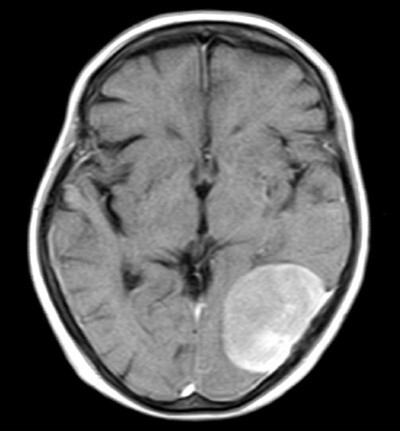

21

Q

Double Vision (Diplopia) and headache. MRI will show a ball in the occipital lobe. Blood calcium levels are normal (no affect on calcium)

Meningioma (Psammoma bodies)

Meningioma CT